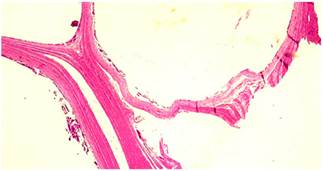

La pieza quirúrgica se envió al servicio de patología, en el que se reconoció un segmento colónico de 15 cm con diámetros variables de 2 a 4 cm, seroso de color pardo claro cubierto en toda su extensión por un mesenterio que medía hasta 4 cm. La mucosa se había remplazado en más del 80 % por formaciones quísticas de aire, la mayor de ellas medía 4,5 x 4 cm y la menor, 2 x 1 cm; con una pared que medía 0,1 cm; estas lesiones también se pudieron observar de menor tamaño en el mesenterio circundante (Figura 2). Además, en el análisis microscópico se encontró en la submucosa y la capa muscular propia múltiples lesiones quísticas (Figura 3), asociadas con células gigantes multinucleadas tipo cuerpo extraño y macrófagos (Figura 4). Las lesiones se extendieron hasta la subserosa, donde también se observaron células mesoteliales reactivas. Con estos hallazgos se confirmó el diagnóstico de neumatosis quística intestinal.

Macroscópicamente, la neumatosis intestinal se caracteriza por múltiples estructuras similares a quistes en la mucosa de la pared intestinal, en algunas ocasiones se describe con aspecto cerebriforme. Microscópicamente, se reconocen estructuras similares a quistes de tamaño variable sobre la mucosa, submucosa o muscular propia con tamaños desde milímetros hasta algunos centímetros; como características histológicas, estas estructuras están revestidas por macrófagos, células gigantes multinucleadas tipo cuerpo extraño e infiltrado inflamatorio mononuclear 3. Los quistes tempranos pueden estar revestidos por células endoteliales, por lo que se puede interpretar en algunas ocasiones como distensión de los vasos linfáticos 11.